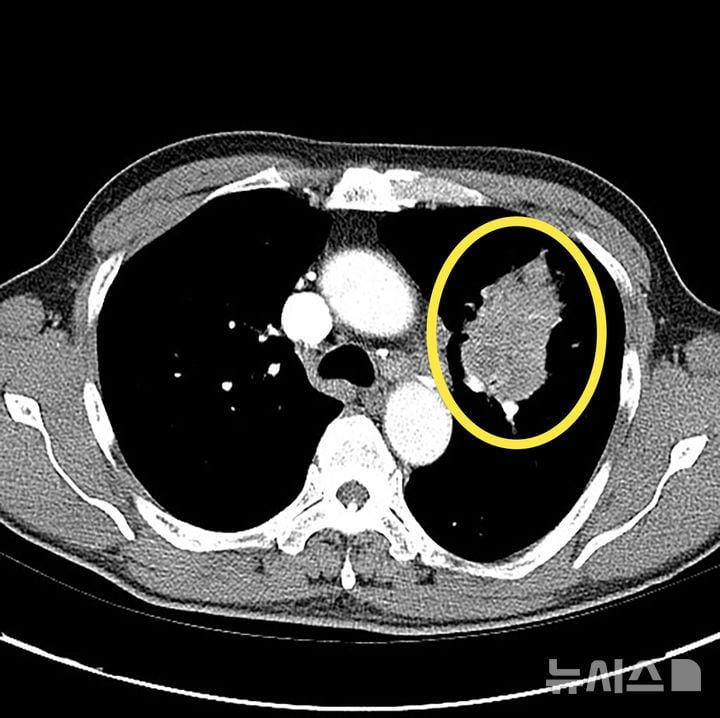

저선량 CT는 폐 내 작은 결절까지 탐지할 수 있으면서, 환자에게 노출되는 방사선을 기존 검사의 6분의 1 수준으로 줄인 영상 진단 기술이다. 특히 흡연 경험이 있거나 가족력, 미세먼지 등 고위험 환경에 장기 노출된 사람, 만성 폐질환 환자에 대해 정기 검사가 권장된다. 전문가들은 폐암 5년 상대 생존율이 41%에 불과하지만, 전이가 없는 조기 진단은 생존율이 80%까지 대폭 높아진다며 정기 검진의 산업적·의료적 효과가 크다고 분석한다.